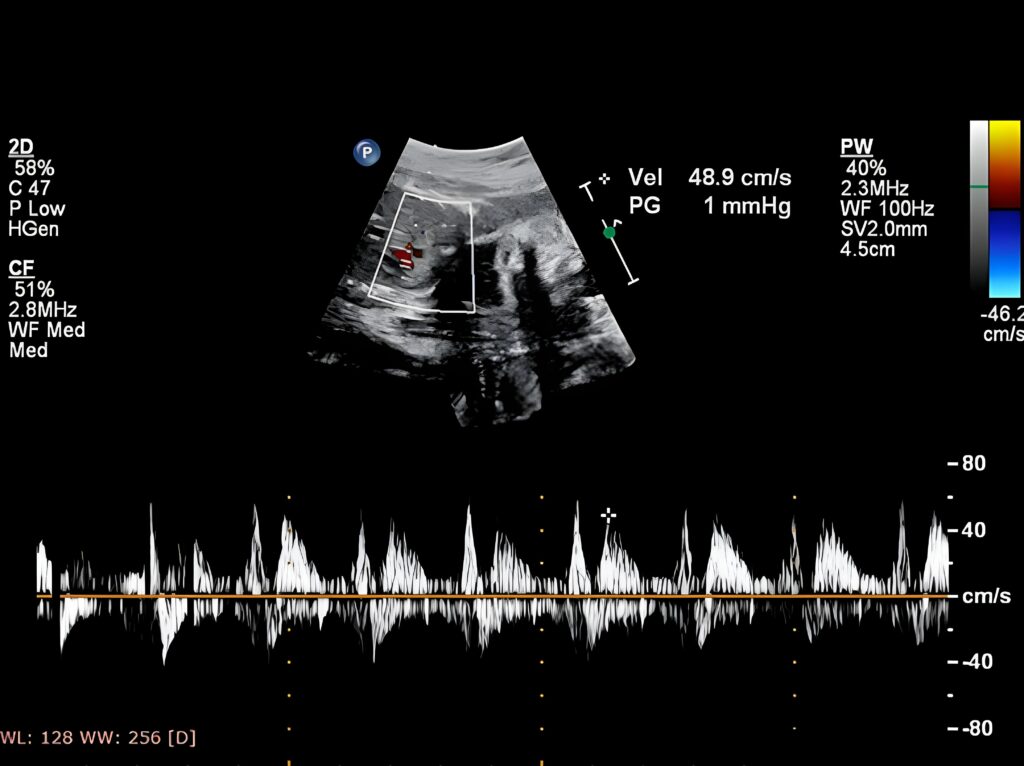

ECOCARDIOGRAFIA FETAL

• Módulo 1: Introdução a Ecocardiografia Fetal

• Módulo 2: Cardiopatias Congênitas

• Módulo 3: Malformações Cardíacas fetal I

• Módulo 4: Malformações Cardíacas fetal II

• Módulo 5: Arritmias cardíacas

Dentro desse contexto e com o avanço das tecnologias de imagem, a ecocardiografia fetal tornou-se uma ferramenta indispensável para a detecção precoce de anomalias cardíacas durante a gestação. Este curso abrangente cobre os princípios fundamentais da ecocardiografia, incluindo técnicas de imagem, interpretação de resultados e identificação de malformações cardíacas congênitas.